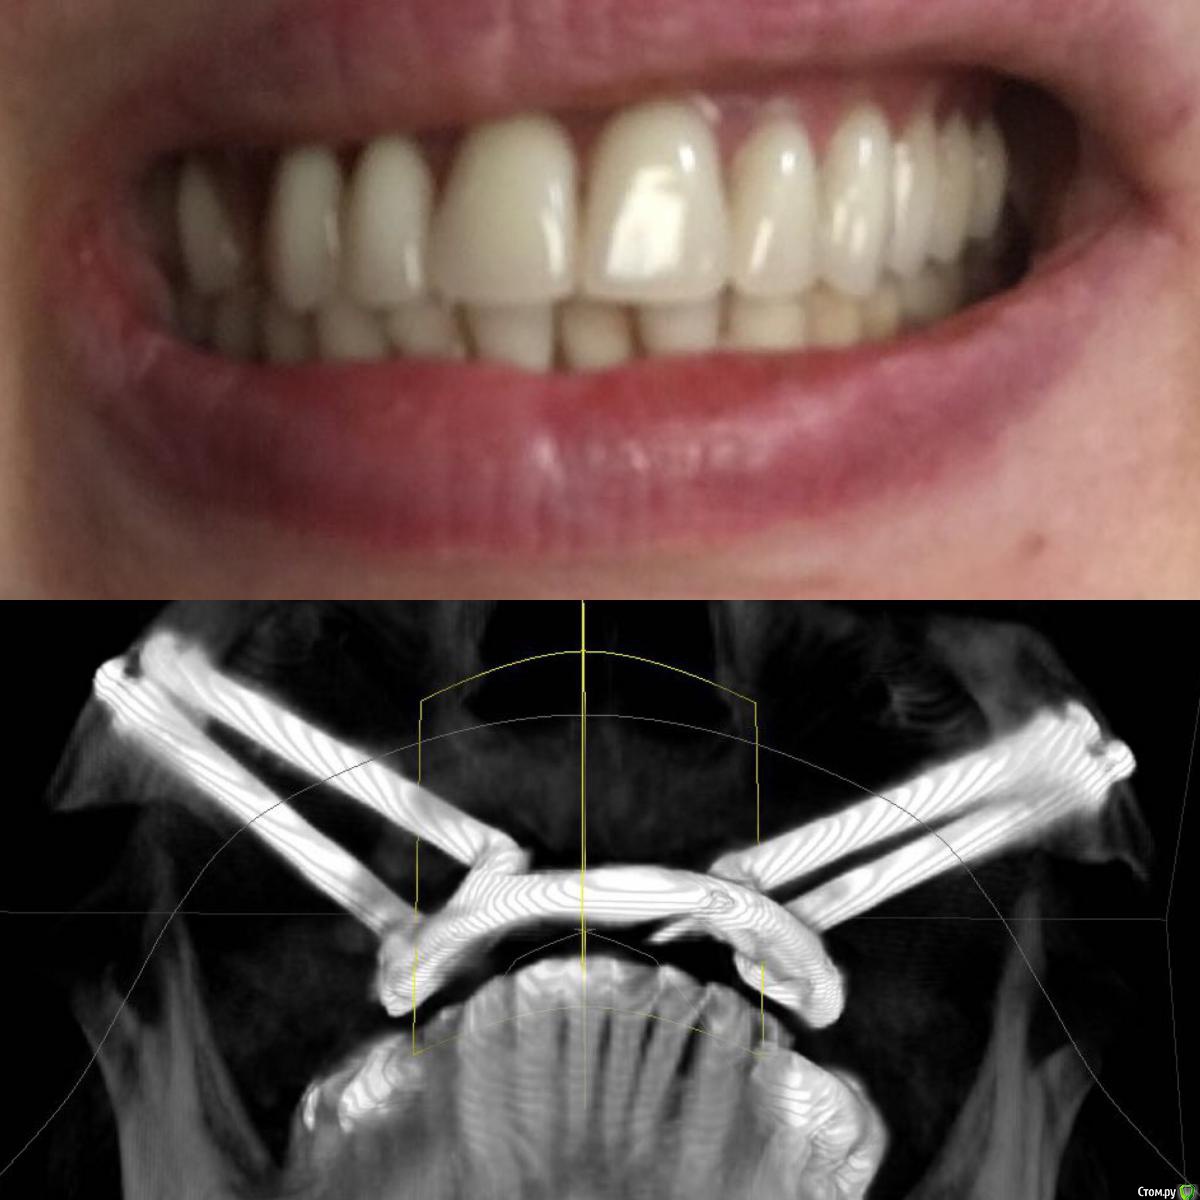

Maggie78rus Опубликовано 20 марта, 2017 Автор Поделиться Опубликовано 20 марта, 2017 (изменено) https://drive.google.com/open?id=0B5M5deCMkPdRdExpV1RRdTRGZ3MВот, присоединила некоторые фотографии. Прошу извинить за демонстрируемый кошмар, поверьте, мне ещё и больно плюс я не могу держать равновесие Разыскиваю хорошего ортопеда в Санкт-Петербурге. Слышала много вариантов лечения вплоть до ортогнатологической операции и переделки конструкции заново на других имплантатах. Изменено 20 марта, 2017 пользователем Maggie78rus Ссылка на комментарий

Maggie78rus Опубликовано 20 марта, 2017 Автор Поделиться Опубликовано 20 марта, 2017 ортопед это и есть "протезист" Ортодонт вам не нужен. Зубов то нет. Честно говоря данных мало. Почему надо ставить зигомы не ясно.Мне тоже не совсем ясно, зачем мне удалили одни имплантаты и поставили на другие протез с такой же окклюзией. Все, конечно, путается в голове от этого нескончаемого кошмара и , извините, зубной боли, хотя зубов уже 2 года нет- потеряла после первого протезирования. Очень устала.Проблему с окклюзией, я получила 8 лет назад.Тогда я ничего не могла сделать, не могу сделать ничего и сейчас. Какое-то дежавю: милые стоматологи встречают меня с распростертыми объятиями, берут деньги, потом у них ничего не получается, т.к. все снимали анатомические слепки и по ним отливали мосты, а теперь протез... Никто не пользовался артикулятором и лицевой дугой. Я приходила к врачам, надеясь получить качественную стоматологическую помощь. Для установки скуловых имплантатов мне даже обещали использовать высокие шведские технологии трёхмерного моделирования... но, погрузив меня в медикаментозный сон, опять сняли оттиск и отлили протез по образу и подобию того, что я так стремилась исправить: страшного, маленького, заваленного то на один, то на другой бок.И так три раза. У меня отваливался то передний зуб, то клык...ничто не убеждало врача сделать дугу об'емнее...в конце-концов я настояла на диагностике у гнатолога, но диагностические модели разбили в окклюдаторе.В Клинике все врачи -специалисты широкого профиля да ещё и лекции читают, но мне-то они помочь не могут и не хотят: они уже получили все деньги, извините, обманом, а у меня ещё не стоит временный протез с нормальной окклюзией.Что делать? Ума не приложу! То, что зубов нет и ты не чувствуешь, как идёт нагрузка от зубов, думаю, неправда. Чувствуешь. Чувствуешь, как нёбный шов уходит в сторону...Попросила собрать консилиум врачей, чтобы помочь советами - результат один- делают оттиск, потом делают вид, что моделируют на воске, иногда получается здорово! Но потом ставят все тот же оттиск, но под другим углом Ссылка на комментарий

Maggie78rus Опубликовано 20 марта, 2017 Автор Поделиться Опубликовано 20 марта, 2017 У меня центр верхней и нижней челюстей не совпадают. Не знаю было так или нет. Потом у меня небо не плоское и деформированное от неправильной нагрузки на мосты , а теперь его протез на зигомах дожимает, больно Ссылка на комментарий

Maggie78rus Опубликовано 30 марта, 2017 Автор Поделиться Опубликовано 30 марта, 2017 Состоявшая "дискуссия" лишний раз подтвердила, что Зигомам пациентам надо сказать НЕТ. Проблем они не решают, а лишь добавляют, особенно тяжело установить на них грамотную ортопедическую конструкцию: несмотря на то, что методика имплантации авторская и требует предварительной диагностики, четкого планирования и соблюдения Протокола проведения операции, недобросовестные хирурги вносят свое НОУ-ХАУ и превращают имплантат с пожизненной мировой гарантией в железяку, на которую гарантия вообще не распространяется и протез не устанавливается. Особенно хочется предостеречь всех желающих получить голливудскую улыбку от врача, который ГАРАНТИРУЕТ ее вам, просит заплатить в карман, не ведет медицинской документации... Ссылка на комментарий